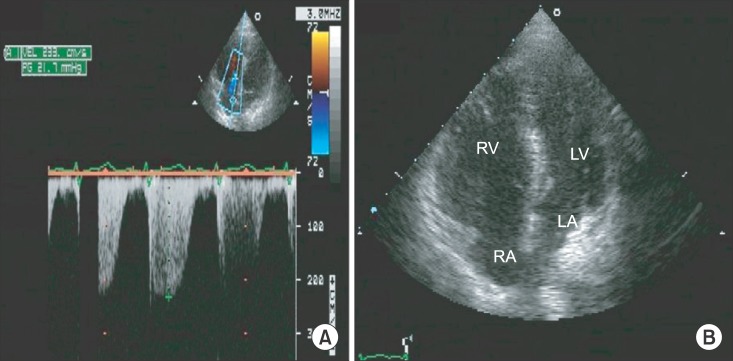

A 31-year-old female patient with a height of 164 cm and weight of 60 kg was admitted to undergo ethanol sclerotherapy for a large painful vascular malformation in her left leg. Magnetic resonance imaging revealed an AVM measuring 28 × 7 × 4 cm in her left calf (Fig. 1). All preoperative examinations, including laboratory tests, electrocardiography, and chest X-ray, were normal. Vital signs before general anesthesia were stable: her blood pressure was 130/80 mmHg and her heart rate was 82 beats/min. Following the application of routine hemodynamic monitoring (3-lead electrocardiogram, noninvasive blood pressure, and pulse oximetry), anesthesia was induced using a bolus intravenous injection of 120 mg propofol and 40 mg rocuronium. A 20-gauge catheter was inserted into the radial artery to monitor her arterial blood pressure continuously. The target controlled infusion of 2% propofol and remifentanil (2-3 µg/ml and 2-5 ng/ml of the effect-site concentrations, respectively) was applied to maintain anesthesia. Immediately following the injection of ethanol, the patient's blood pressure and heart rate rose slightly to 160/100 mmHg and 100 beats/min, respectively. Thereafter, the patient's blood pressure and heart rate were stable throughout the procedure while she was in the prone position. A total dose of 50 ml of 99% ethanol was injected into the lesion over a period of 30 minutes without the use of a tourniquet. As soon as the patient was turned from prone to supine after finishing the procedure, an abrupt drop in her arterial blood pressure occurred, 40-50 mmHg systolic and 10-15 mmHg diastolic blood pressure with a simultaneous increase in her heart rate to 100-110 beats/min. To restore blood pressure, 20 mg of ephedrine was immediately injected, but the patient's heart rate rather decreased abruptly to < 30 beats/min. Chest compressions were performed along with the simultaneous injection of 50 µg of epinephrine. A few minutes later, the patient's blood pressure and heart rate recovered to 180/100 mmHg and 100-110 beats/min. At that moment, the arterial blood gas analysis showed metabolic acidosis with otherwise normal findings (pH 7.29, PaCO2 28 mmHg, PaO2 466 mmHg, SaO2 100%, base excess -11.6, Hematocrit 38%, Na+ 137 mEq/l, K+ 3.7 mEq/l, and Ca2+ 1.11 mmol/l). The patient was transferred to the intensive care unit with the endotracheal tube in place. Transthoracic echocardiograph (TTE) and embolism computed tomography (CT) were performed to confirm pulmonary hypertension or pulmonary embolism. There was no evidence of pulmonary embolism on CT. In addition, the peak tricuspid regurgitation jet velocity on TTE was 2.3 m/s, indicating no evidence of pulmonary hypertension at that moment (Fig. 2A). However, TTE revealed dilated right ventricle (Fig. 2B) and severely decreased right ventricular function.

In our present case, 50 ml of 99% ethanol was injected into a 60 kg patient. The total dose of ethanol that was injected was nearly the maximum dose allowable for this patient. The large amount of ethanol that was injected might have carried a potential risk of cardiovascular compromise, or the right heart failure was caused by the acute development of severe pulmonary hypertension. We could not find any direct evidence of pulmonary hypertension because the normal peak tricuspid regurgitation jet velocity on our TTE examination was observed. Nevertheless, we speculate that the right heart failure mainly contributed to the development of cardiovascular collapse in this case, that is, a systematically absorbed ethanol may result in severe pulmonary hypertension acutely, leading to right heart failure which was inferred from a dilated right ventricle and severely poor right ventricular function on TTE examination. The normal peak tricuspid regurgitation jet velocity would likely manifest due to right ventricle dilatation which persisted as the trace of acute severe pulmonary hypertension. As a result of right heart failure, left ventricular filling and output decreased, eventually leading to cardiovascular collapse which necessitated the prompt resuscitation.